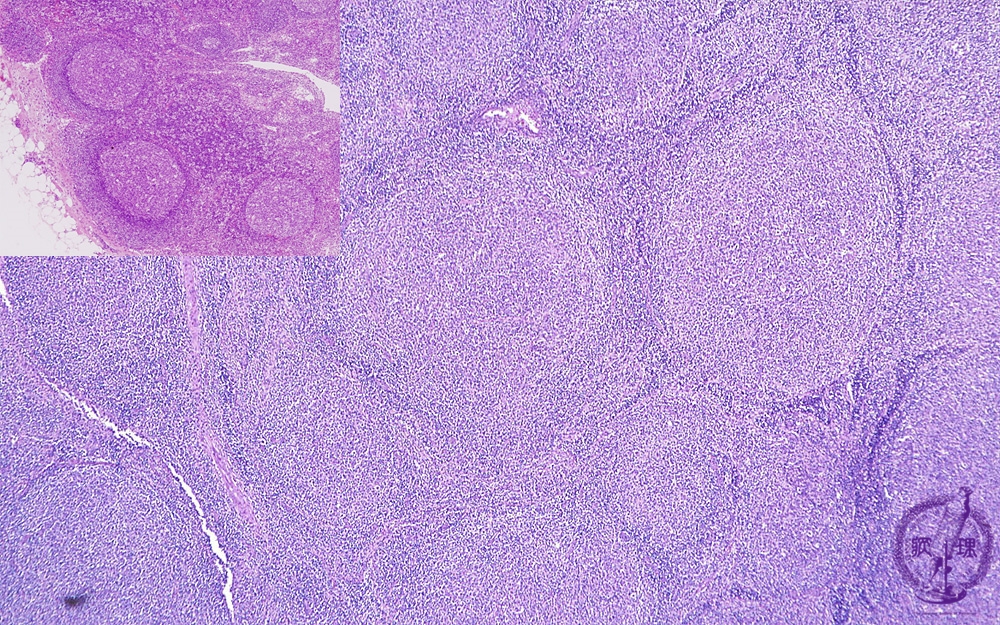

- 2.Lymph node

- (5)Follicular lymphoma

Microscopic image (H&E low power view): There are numerous large follicles with indistinct borders and these typically efface the entire lymph node architecture. These neoplastic follicles are variably spaced and may be confluent. In contrast, non-neoplastic interfollicular spaces are typically wide (upper left inset).